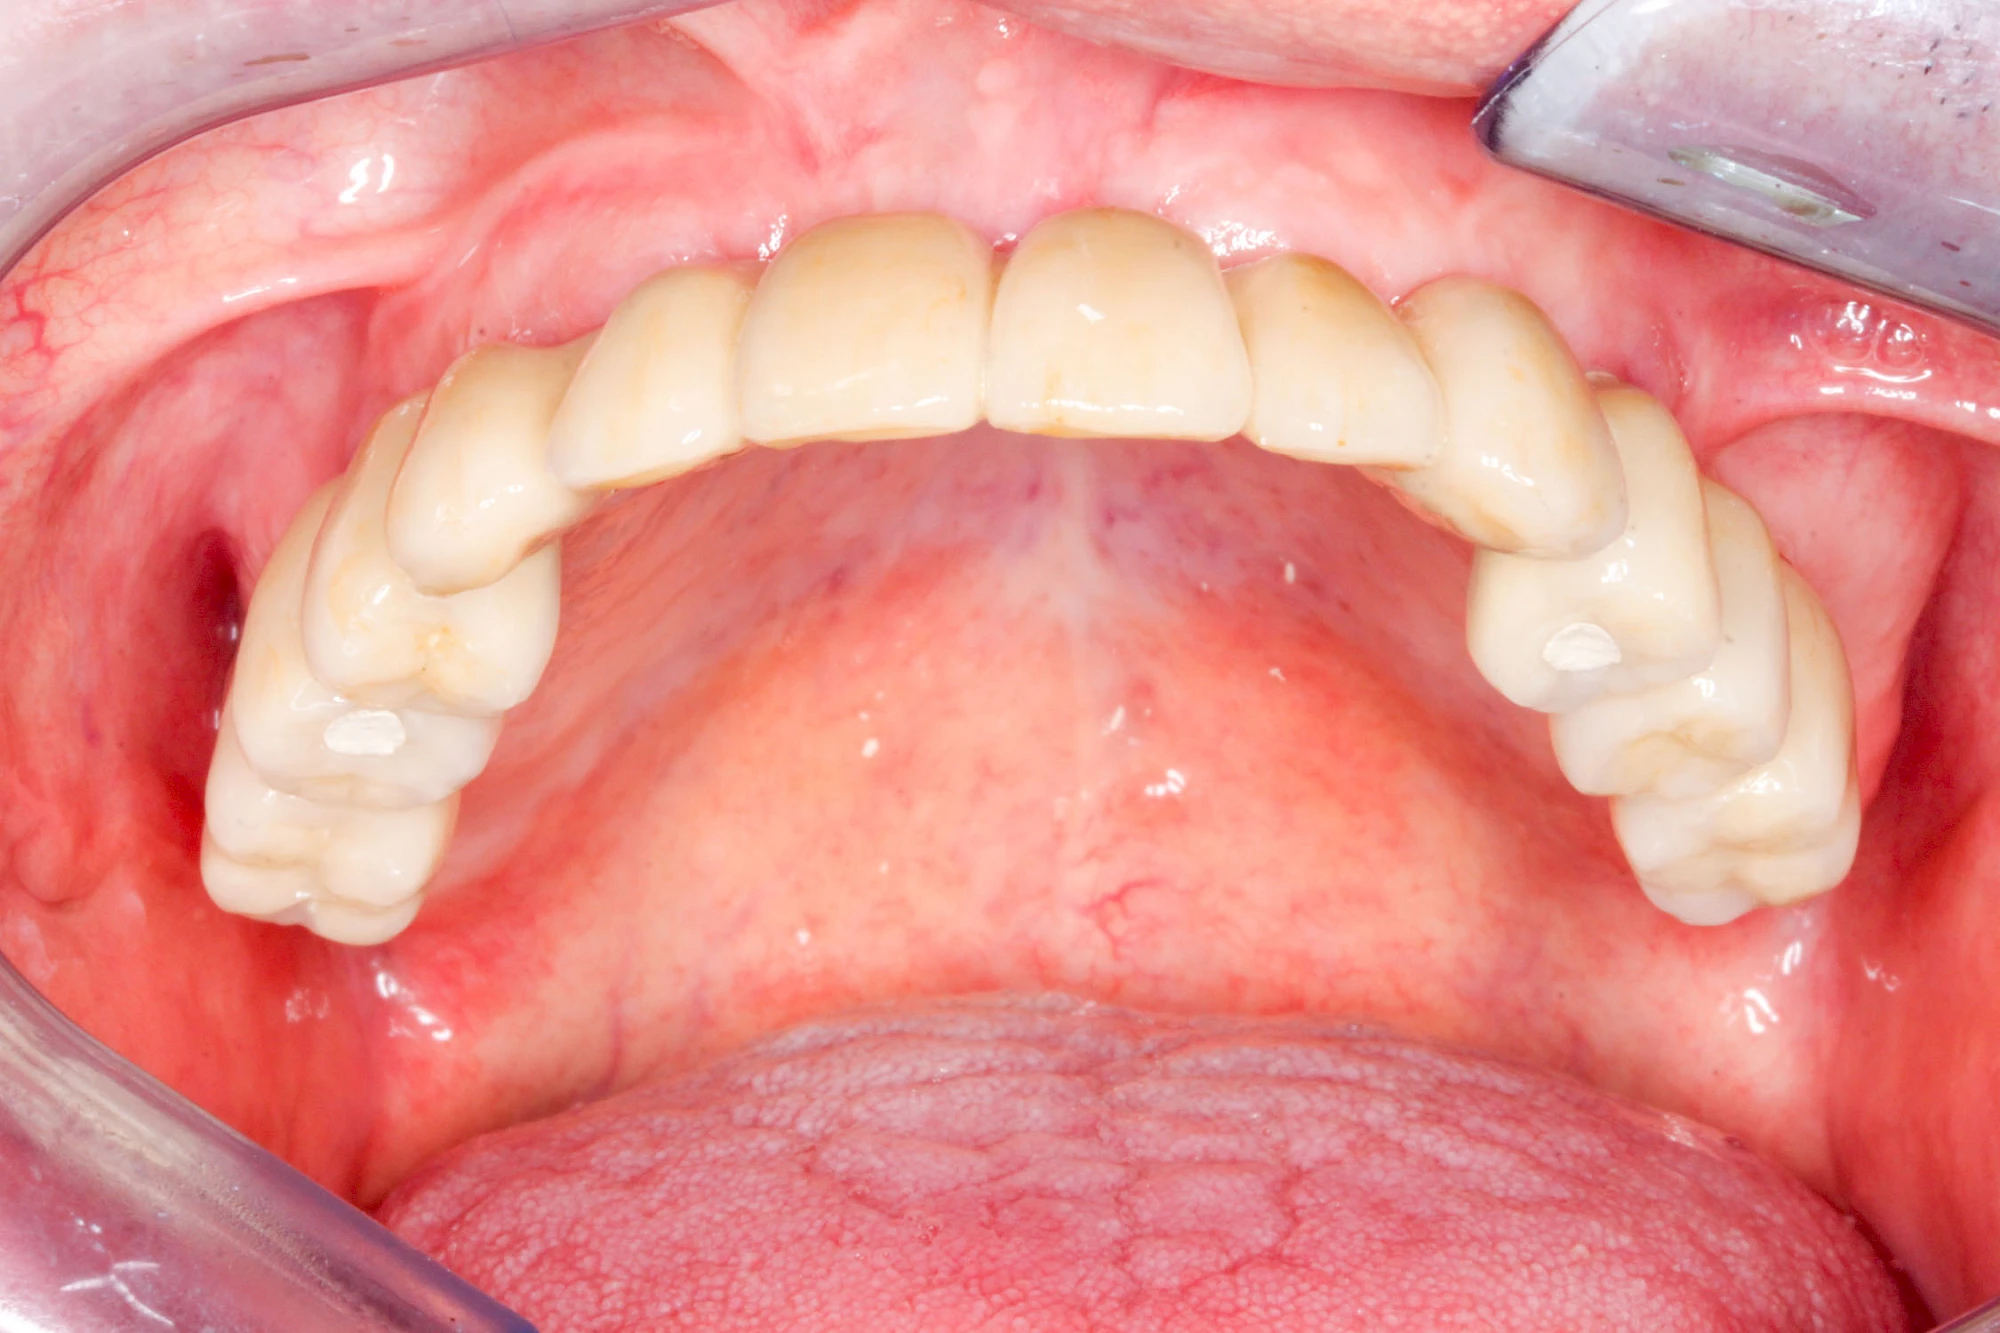

Fehlen einzelne Zähne und die Nachbarzähne sind unbeschadet oder gut zahnärztlich versorgt, werden immer häufiger Implantate gewählt, um die Lücken zu schließen. Auch bei größeren oder verteilten Lücken, wenn keine herausnehmbare Prothese gewünscht ist, werden Implantate für Kronen- bzw. Brückenversorgungen gesetzt. In Einzelfällen entscheiden sich sogar zahnlose Patienten für eine festsitzende Versorgung auf Implantaten.

Varianten zur Verankerung von festsitzendem Zahnersatz auf Implantaten